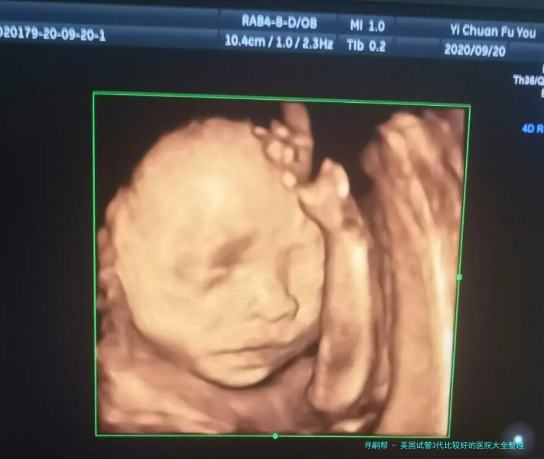

试管婴儿越发越多的不孕家庭通过试管婴儿来实现生育愿望。本文将为你介绍美国比较好的五家试管3代医院,分别从费用、成功率和医疗装置等方面进行介绍。